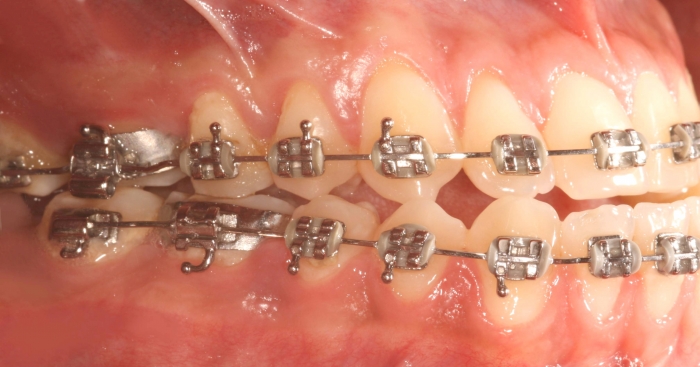

Mordida final